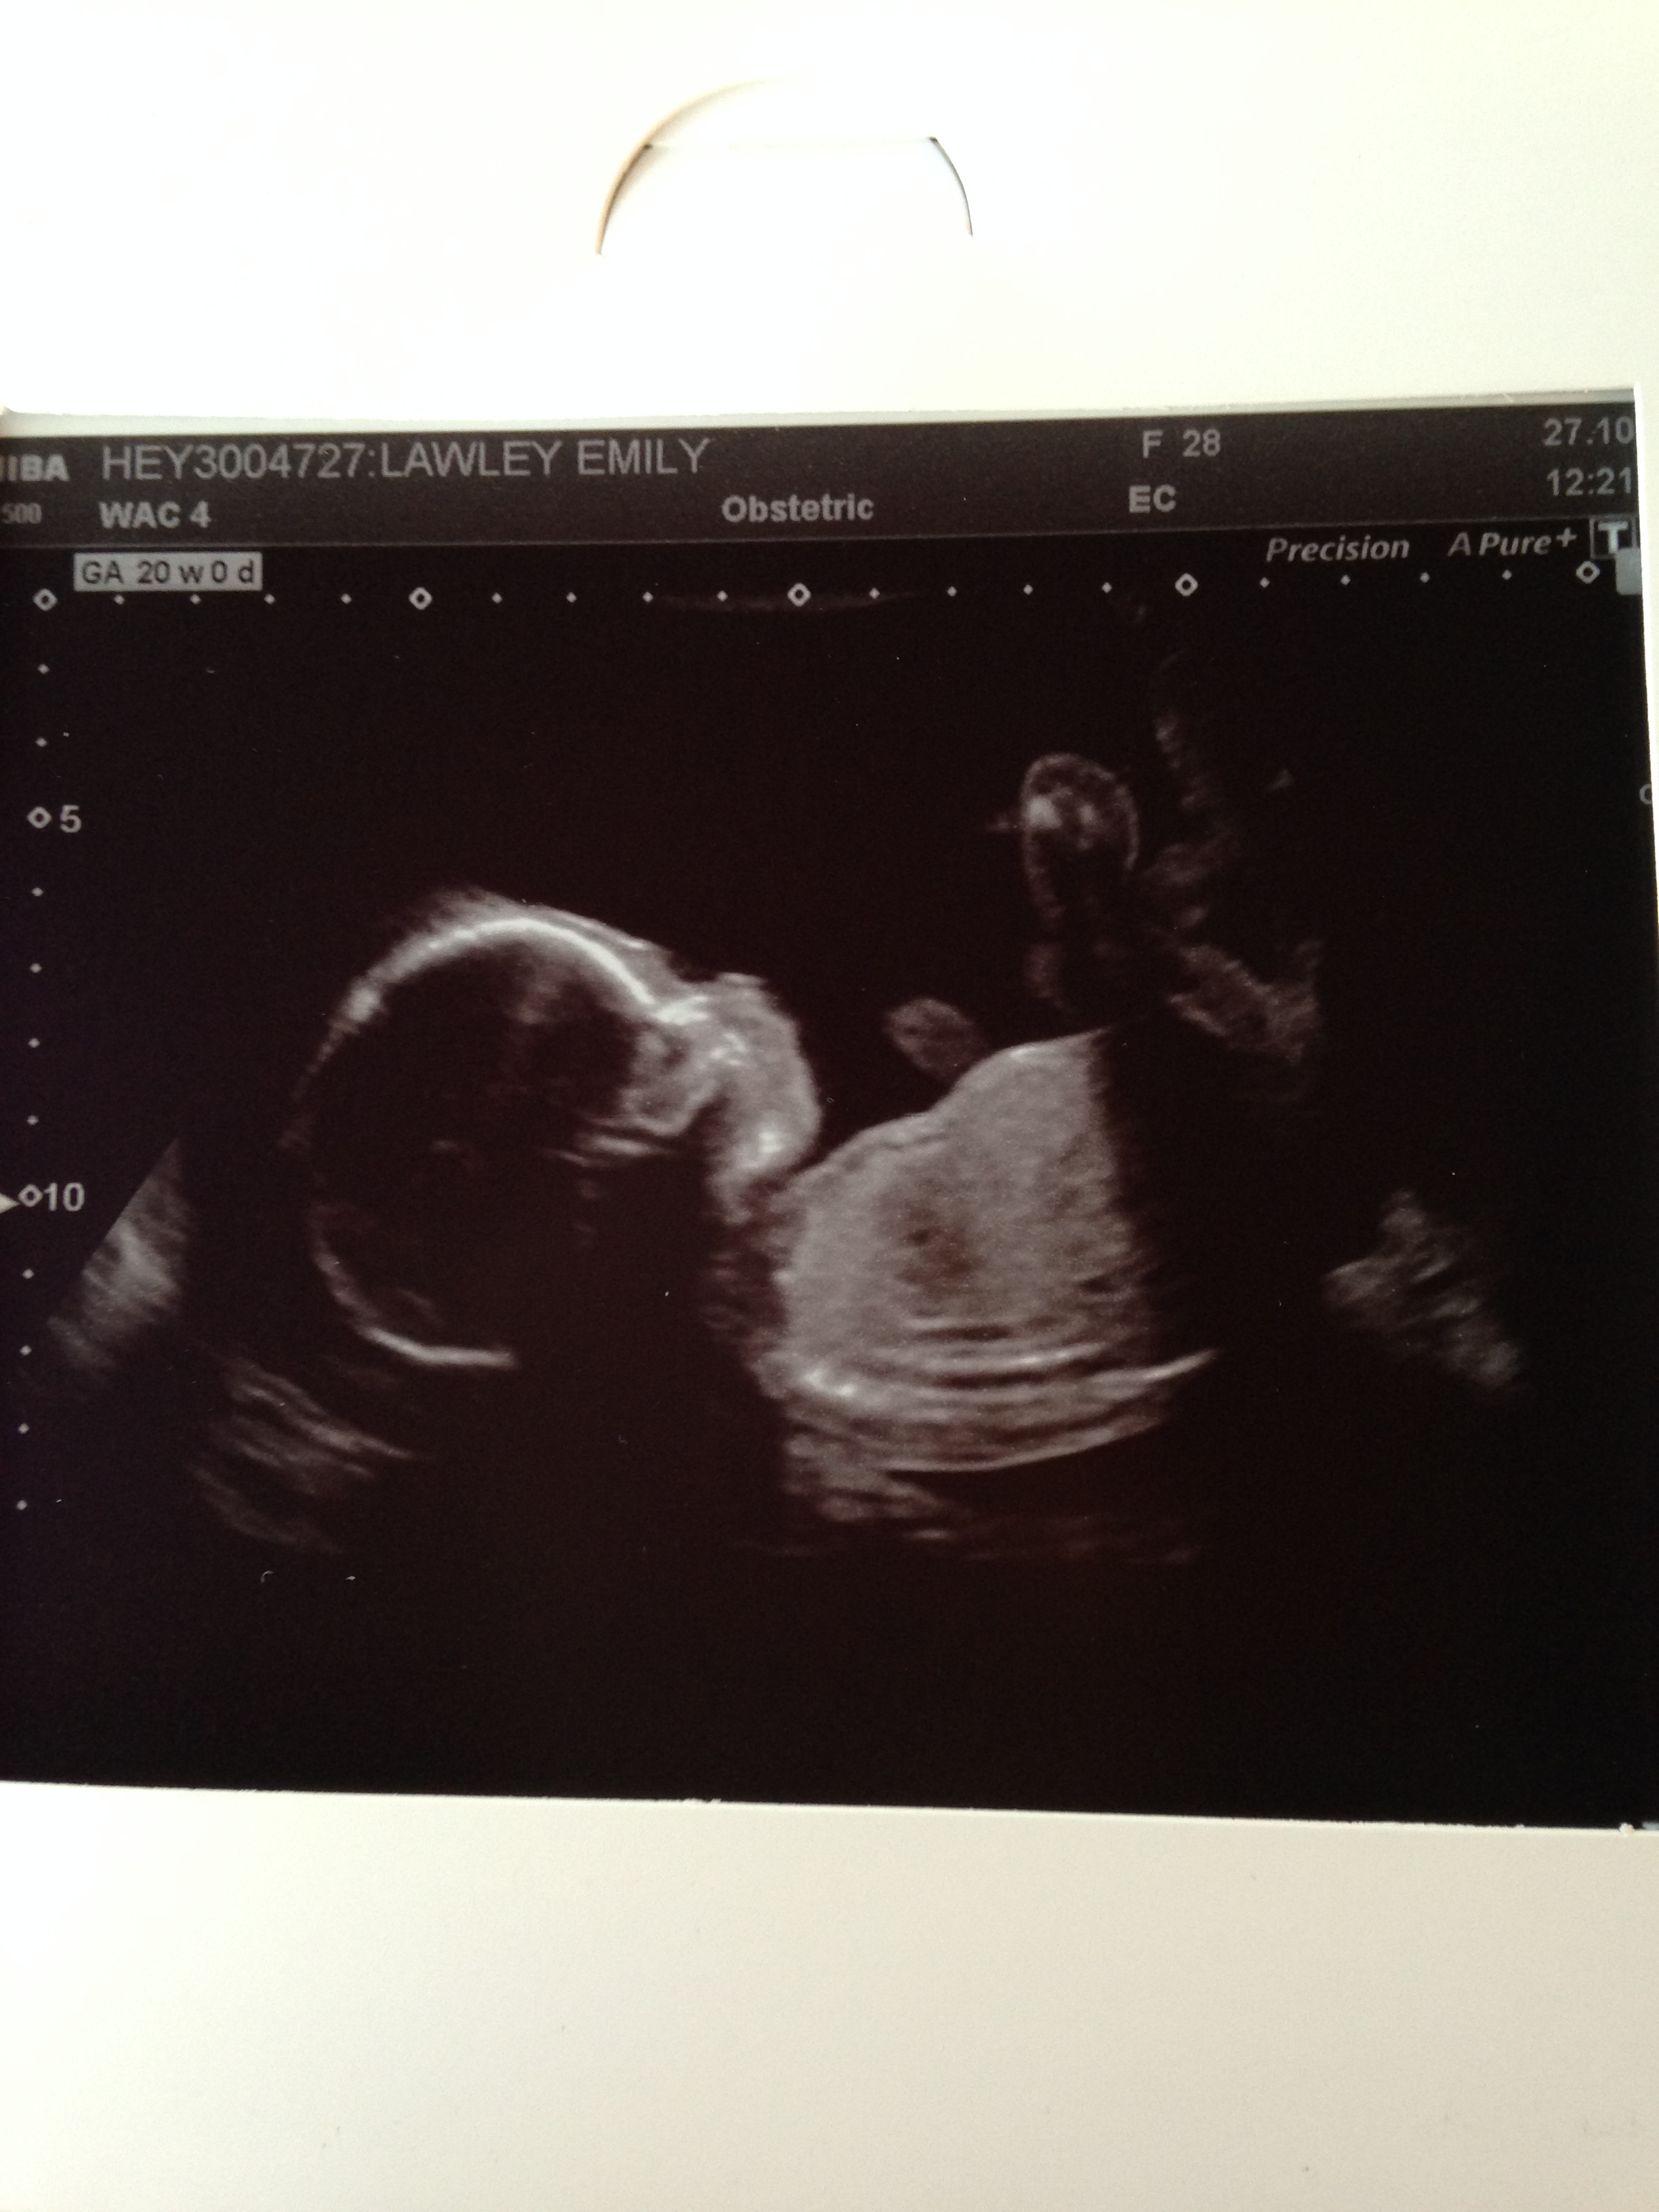

Today is finally the day we can see the baby again. We were both a little nervous about the scan which is to be expected as they check everything thoroughly to make sure the baby is developing normally. Luckily for us everything was perfect and it was fascinating to see their tiny heart beating on the screen, inside their skull and their tiny face and feet! Oh, and we are team neutral still – we didn’t find out if we’re having a girl or a boy. Just 20 weeks to go until we find out…!

After about 15 minutes of the sonographer doing all her checks she then tried to get us a good photo to take away. Unfortunately by this point the baby seemed pretty fed up of being poked and prodded by her and refused to move from one position. This resulted in the only shot of them being a face-on slightly creepy skull floating on the screen – maybe perfect for Halloween but not for our only other photo of our baby! We tried to get them to move by jiggling about but she finally suggested I got for a walk for 10 minutes before coming back to try again. Luckily this worked as a few of my friends had to come back another day just to get a photo! What a pain.